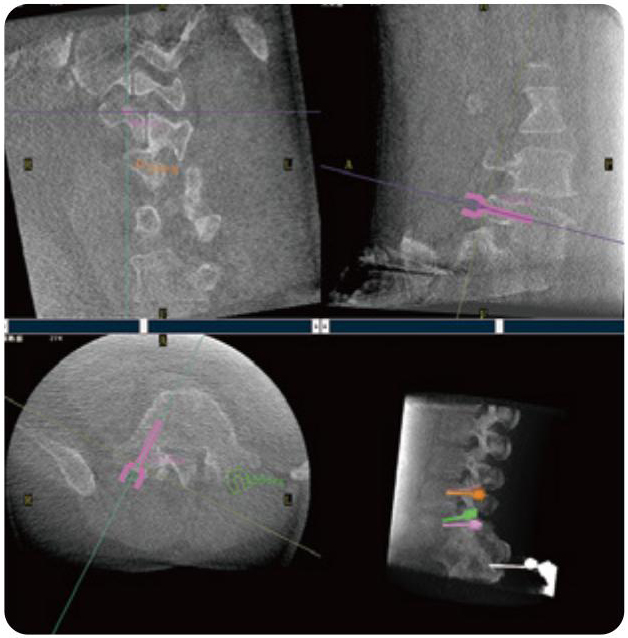

PL300B可應用于多節(jié)段脊柱外科手術,輔助醫(yī)生定位病灶部位,為脊柱外科手術(經(jīng)皮椎體成形術、椎弓根螺釘內固定術等術式)提供術前手術流程規(guī)劃、入釘位置、角度可視化引導,模擬仿真入釘輔助。